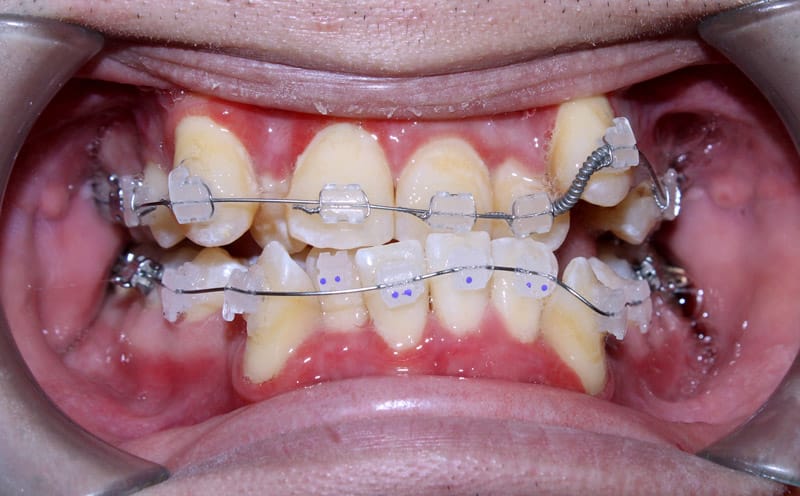

Vệ sinh không đúng cách sẽ rất dễ gây viêm nướu, sâu răng trong quá trình niềng răng

viêm nướu khi niềng răng, tình trạng rất hay gặp nếu không vệ sinh đúng cách, đặc biết với trường hợp răng chen chúc nghiêm trọng